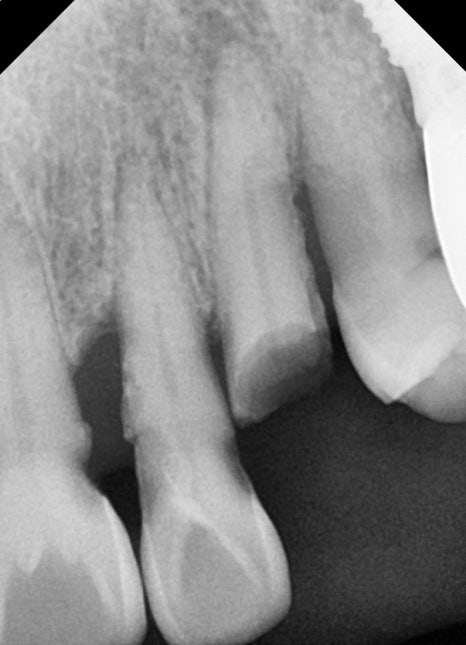

전치부 임플란트가 어려운 이유

앞니 임플란트는

어금니 임플란트보다 훨씬 까다로운 치료입니다.

그 이유는 다음과 같습니다.

잇몸 뼈가 얇음

잇몸 라인이 그대로 노출됨

앞니는 뼈가 얇기 때문에

뼈이식

이 함께 진행되는 경우가 많습니다.

발치와 동시에 진행된 임플란트 식립

이번 케이스에서는

손상된 앞니를 발치한 후

임플란트 식립이 동시에 진행되었습니다.

✔ 전치부 다수 임플란트 식립

✔ 골유도재생술(GBR) 진행

✔ 동종골 이식 병행